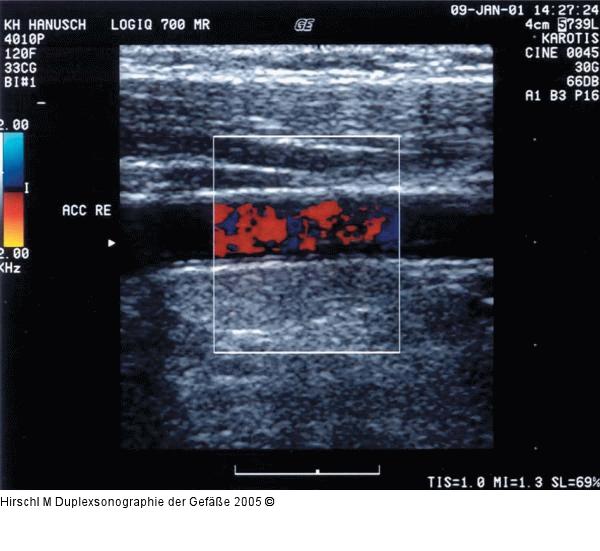

Abbildung 11: Duplexsonographie - Farbfenstereinstellung

Nicht ideal eingestelltes Farbfenster, der Farbfensterwinkel beträgt fast 90° zum Gefäßverlauf, schlechte Farbfensterfüllung. |